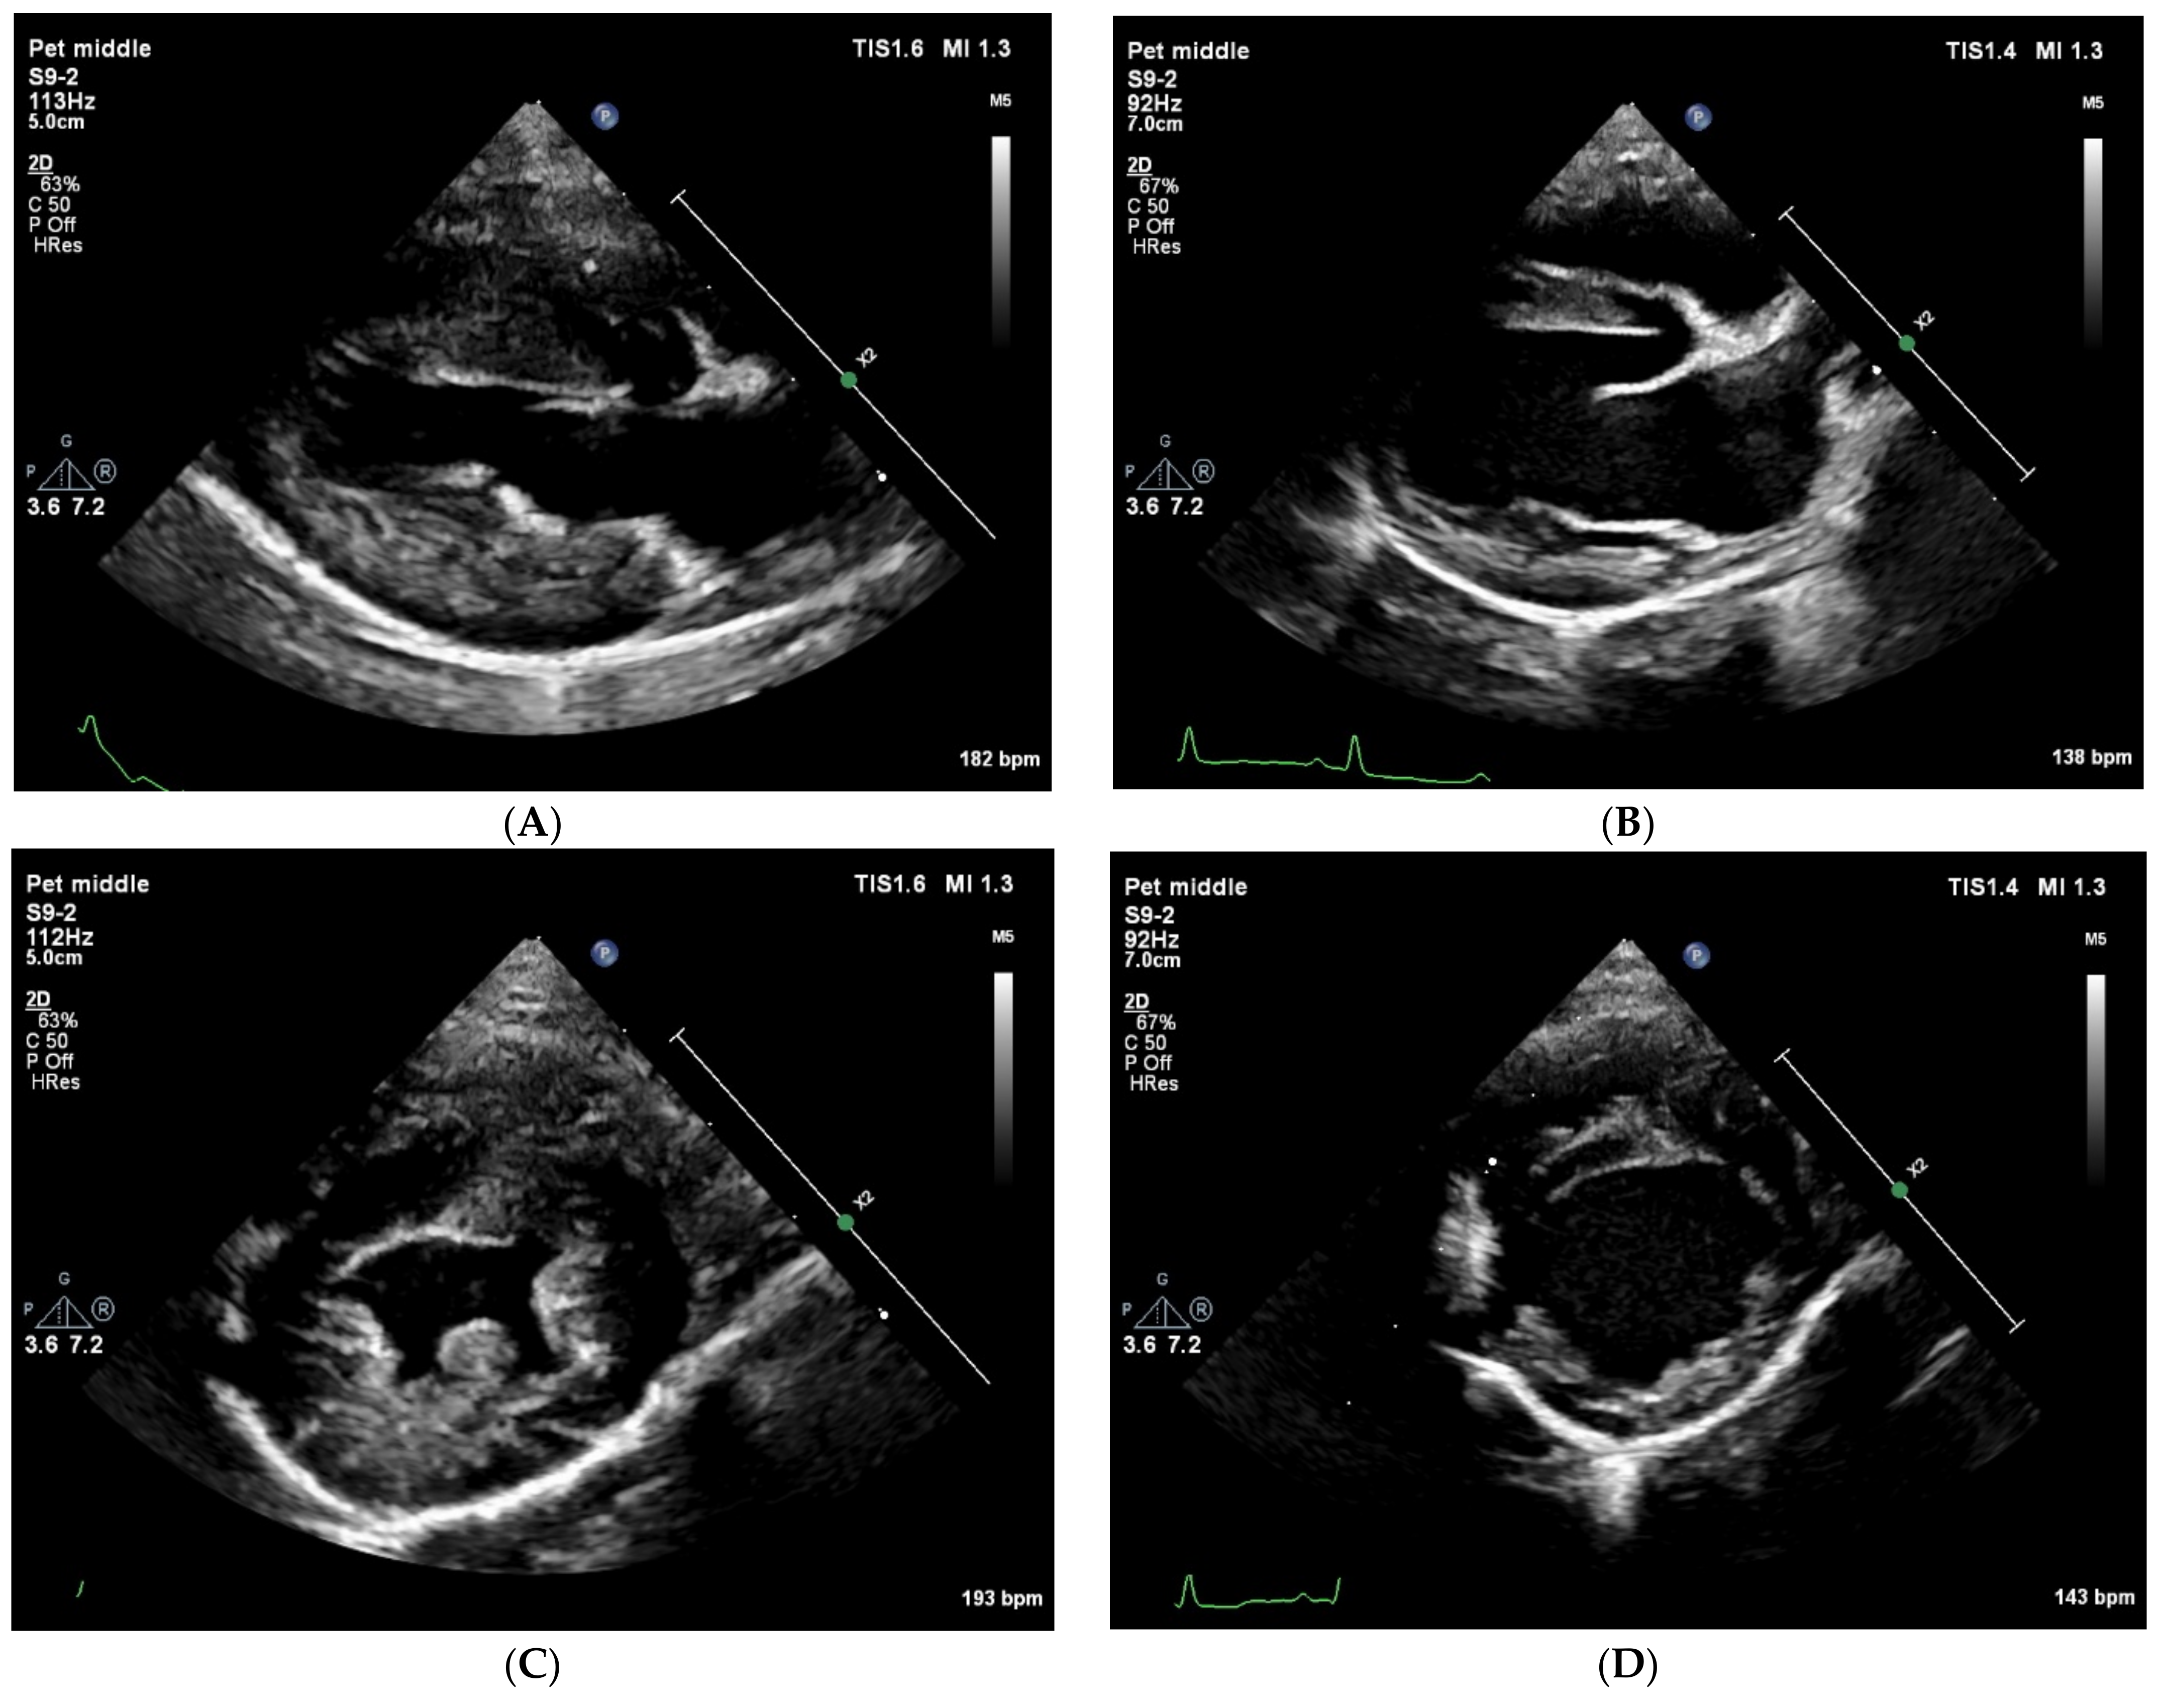

At presentation, the dog was bright, alert, and responsive with a body condition score of 4/9. The respiratory rate was 56 breaths/minute without effort. The femoral pulse quality was fair, and it was symmetrical with a rate of 144 beats/minute. Rectal temperature was 38.9 degrees Celsius. The buccal mucous membranes were pink, with a capillary refill time of 1 s. Cardiac auscultation revealed no murmur or arrhythmia. During a short walk within the clinic from the reception area to the cardiology room, the dog collapsed. During this episode, the femoral pulses could not be felt. Surface electrocardiogram was performed immediately, which showed sinus tachycardia with a rate of 200 beats/minute. Echocardiography showed a severe left ventricular underfilling with severe concentric (pseudo) hypertrophy (Figure 1), and a low peak aortic flow velocity measured from the subcostal view (Table 1). Blood tests were performed. Serum troponine-I concentration was within the reference range (0.01 ng/mL; reference interval [RI], <0.06 ng/mL) making a primary left ventricular hypertrophy unlikely. Basal cortisol concentration (323 nmol/L; RI, >55 nmol/L) was high enough to rule out hypocortisolism. The antigen test for Angiostrongylus vasorum infection was negative. N-terminal pro Brain Natriuretic Peptide (NT-proBNP) concentration was moderately elevated to 971 pmol/L. A 24 h Holter ECG was performed, which revealed sinus tachycardia during the two syncopal episodes that occurred during the registration. The heart rate during the registration varied between 32 and 265 beats/minute, and it was a sinus rhythm with occasional premature atrial complexes, maximal 3 beats/hour.

Twelve days after the initial visit a second consultation was planned. Blood pressure measurements on multiple extremities were performed to rule out aortic coarctation as a possible cause of the left ventricular concentric hypertrophy. Systolic blood pressure measured on the tail, a front leg, and a hind leg excluded aortic coarctation. Echocardiography was repeated and showed no abnormalities at all. Left ventricular internal and wall dimensions (Figure 1) as well as the peak aortic flow velocity were all within reference ranges (Table 1).

Figure 1. Transthoracic right parasternal two-dimensional grey-scale echocardiographic images at initial presentation (A,C) and 12 days later (B,D). All images show an end diastolic frame. Standard longitudinal four-chamber images (A,B) and standard short-axis images at the level of the papillary muscles (C,D) show at the initial presentation a severe underfilling of the left ventricle with severe concentric pseudohypertrophy, and normal wall- and lumen-dimensions 12 days later.